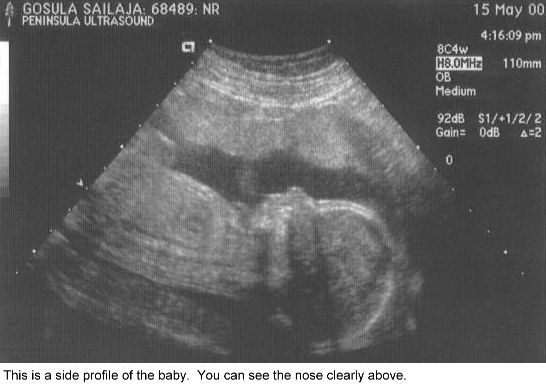

B18weeks2.jpg